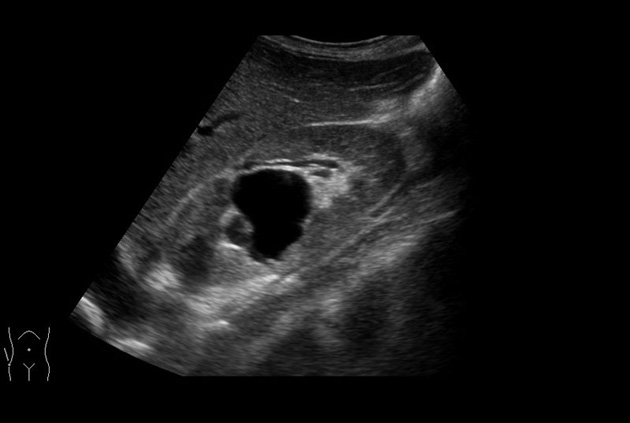

The Arietta 70 has many advanced and unique probes that fully cover the expanding range of procedures that benefit from ultrasound guidance.

Arietta 70’s ergonomics address every point of interaction between the ultrasound system and surgeon. In addition to its moveable control panel, adjustable monitor, and portable frame, the Arietta supports a set of lightweight, ergonomically-contoured and specifically designed surgical probes.